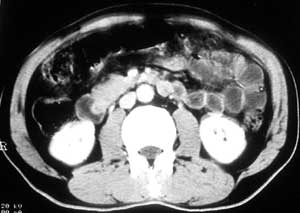

患者,男,57岁,梗阻性黄疸10余天。

这个病例胰头无明显增大,胆总管扩张明显而肝内胆管扩张更不明显,病程较短,

注意到十二指肠乳头明显突出,但尚光滑。分析以下可能性:

1、十二指肠乳头本身的病变,如乳头炎症;

2、急性乳头水肿,胆总管下端结石排石后乳头水肿;

3、壶腹部胆总管下端肿瘤累及十二指肠乳头。

十二指肠乳头粘膜慢性非特异性炎症